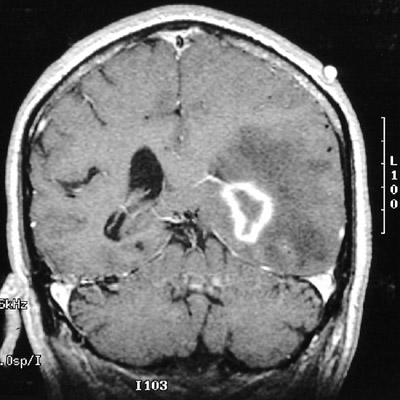

| This MRI scan in coronal view demonstrates a cerebral abscess with bright ring enhancement. There is cerebral edema in adjacent cortex as a consequence, resulting in a mass effect with effacement of the lateral ventricle on the left. Aspergillus was cultured. |